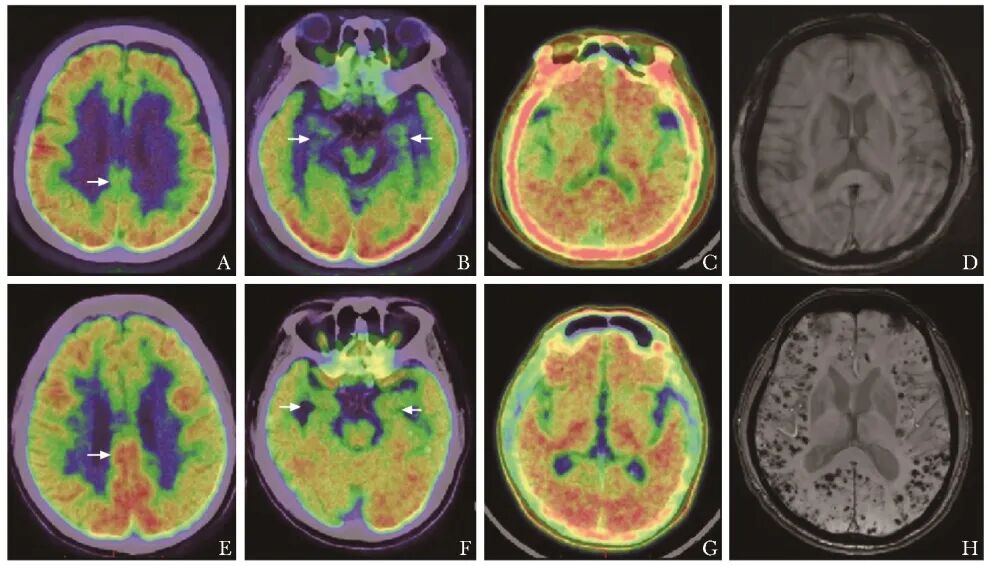

与对照组比较,AD组典型表现为双侧基本对称的颞顶叶代谢减低,以颞叶内侧、后扣带回代谢减低最为显著(图1A~1D)。CAA组皮层代谢减低区呈无特定规律分布,代谢减低或缺损区与出血区域相关(图1E~1H)。

图1 75岁女性AD患者,进行性记忆力下降4年余,伴精神、行为异常,MMSE评分19分,18F-FDG PET/CT示后扣带回、双侧颞叶内侧代谢对称性减低(A、B,箭头),18F-AV45 PET/CT示大脑皮质Aβ弥漫沉积(C),头颅SWI未发现皮层或皮层下明确微出血灶(D);58岁男性很可能CAA患者,进行性反应力、记忆力下降5年余,双下肢乏力、行走变慢3年余,MMSE评分29分,18F-FDG PET/CT示后扣带回代谢保留、双侧颞叶内侧代谢略低(E、F,箭头),余皮层呈无规律、不均匀、不对称多处代谢减低,18F-AV45 PET/CT示大脑皮质Aβ弥漫沉积(G),头颅SWI示双侧大脑半球皮层及皮层下多发微出血灶(H)

AD:阿尔茨海默病;CAA:脑淀粉样血管病;18F-FDG:18F-脱氧葡萄糖;PET/CT:正电子发射断层显像/计算机体层成像;MMSE:简易精神状态检查量表;SWI:磁敏感加权成像